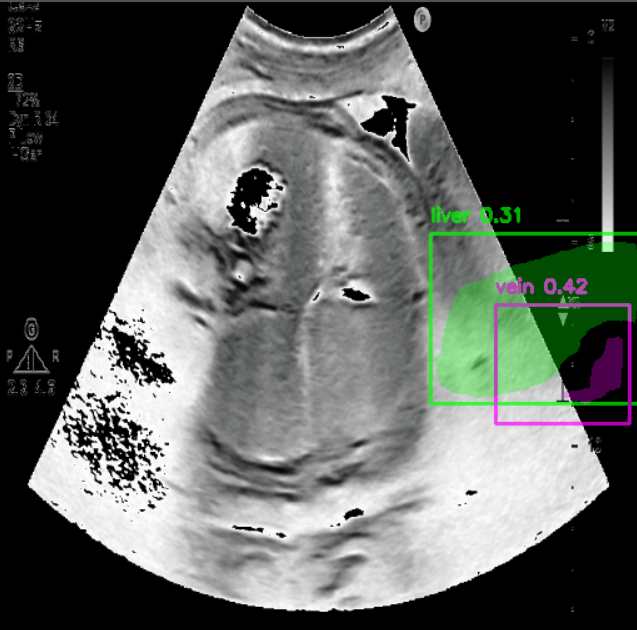

Managed and preprocessed over 10,000 ultrasound images for fetal report generation.

Co-developed healthcare reports that automate fetal health and nutrition analysis.